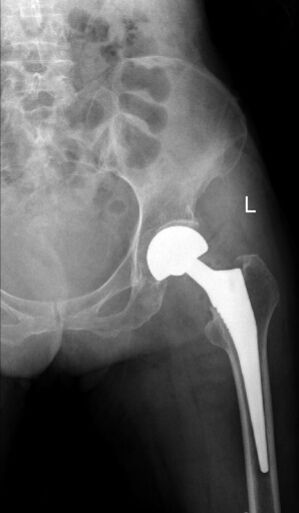

术前x线检查。

2月3日,91岁的肖娭毑因摔倒后左下肢疼痛、不能活动到我院就诊,检查后诊断为:左侧股骨颈骨折(头下型),右侧人工股骨头置换术后。原来,老人10年前因摔跤导致右侧股骨颈骨折,在我院创伤骨病科进行了右侧髋关节置换手术,术后下肢功能活动恢复很好。这次不小心摔跤导致左侧股骨颈骨折,出于对我院创伤骨病科的感情和信任,老人再次选择来我院手术治疗。